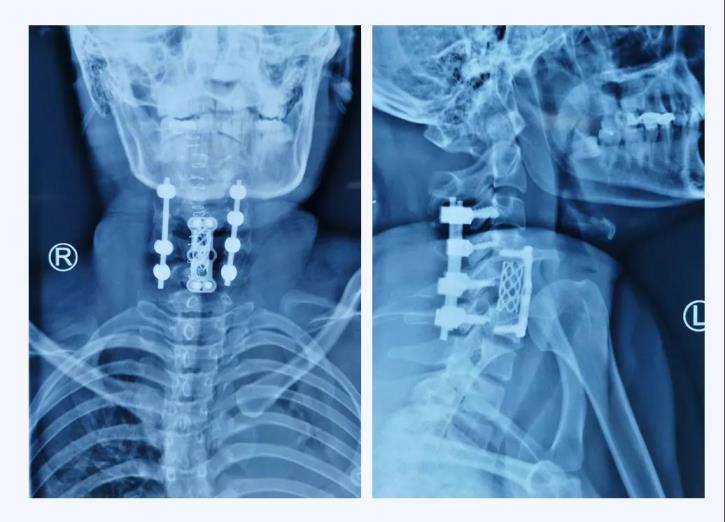

術(shù)后X線

當(dāng)手術(shù)接近尾聲,X線透視機(jī)完美完成術(shù)區(qū)拍攝的一剎那,手術(shù)團(tuán)隊(duì)的所有成員無(wú)不發(fā)出由衷的贊嘆,手術(shù)非常成功!頸椎序列完整的恢復(fù)了!